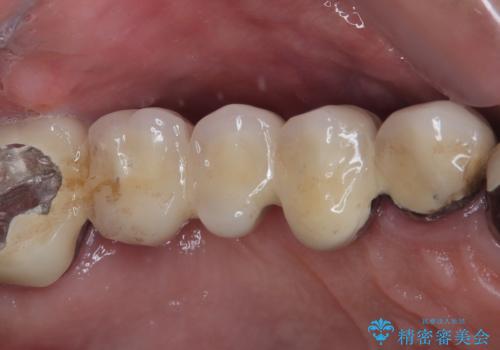

歯周ポケットの除去を併用したセラミック治療